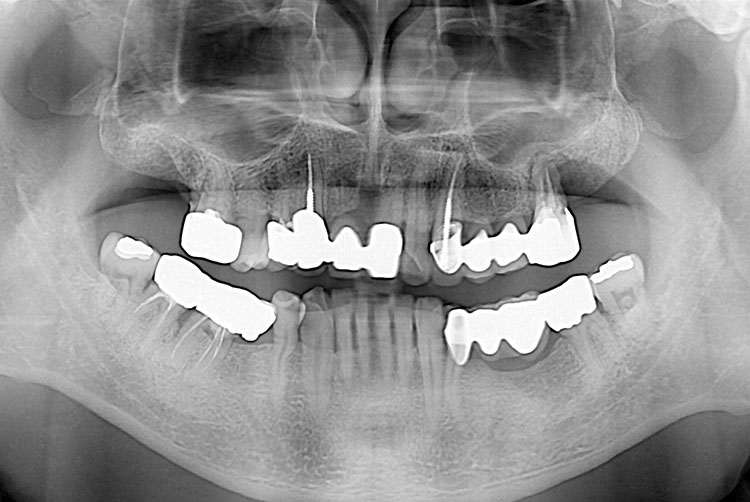

[임플란트] 임플란트

치료후 : 2023-08-18

세종치과는 많은 환자와 다양한 케이스를 바탕으로 항상 편안한 임플란트 수술을 제공하고자 노력하고,

오래동안 튼튼히 쓸 수 있는 임플란트 수술을 가장 큰 목표로 삼고 있습니다.